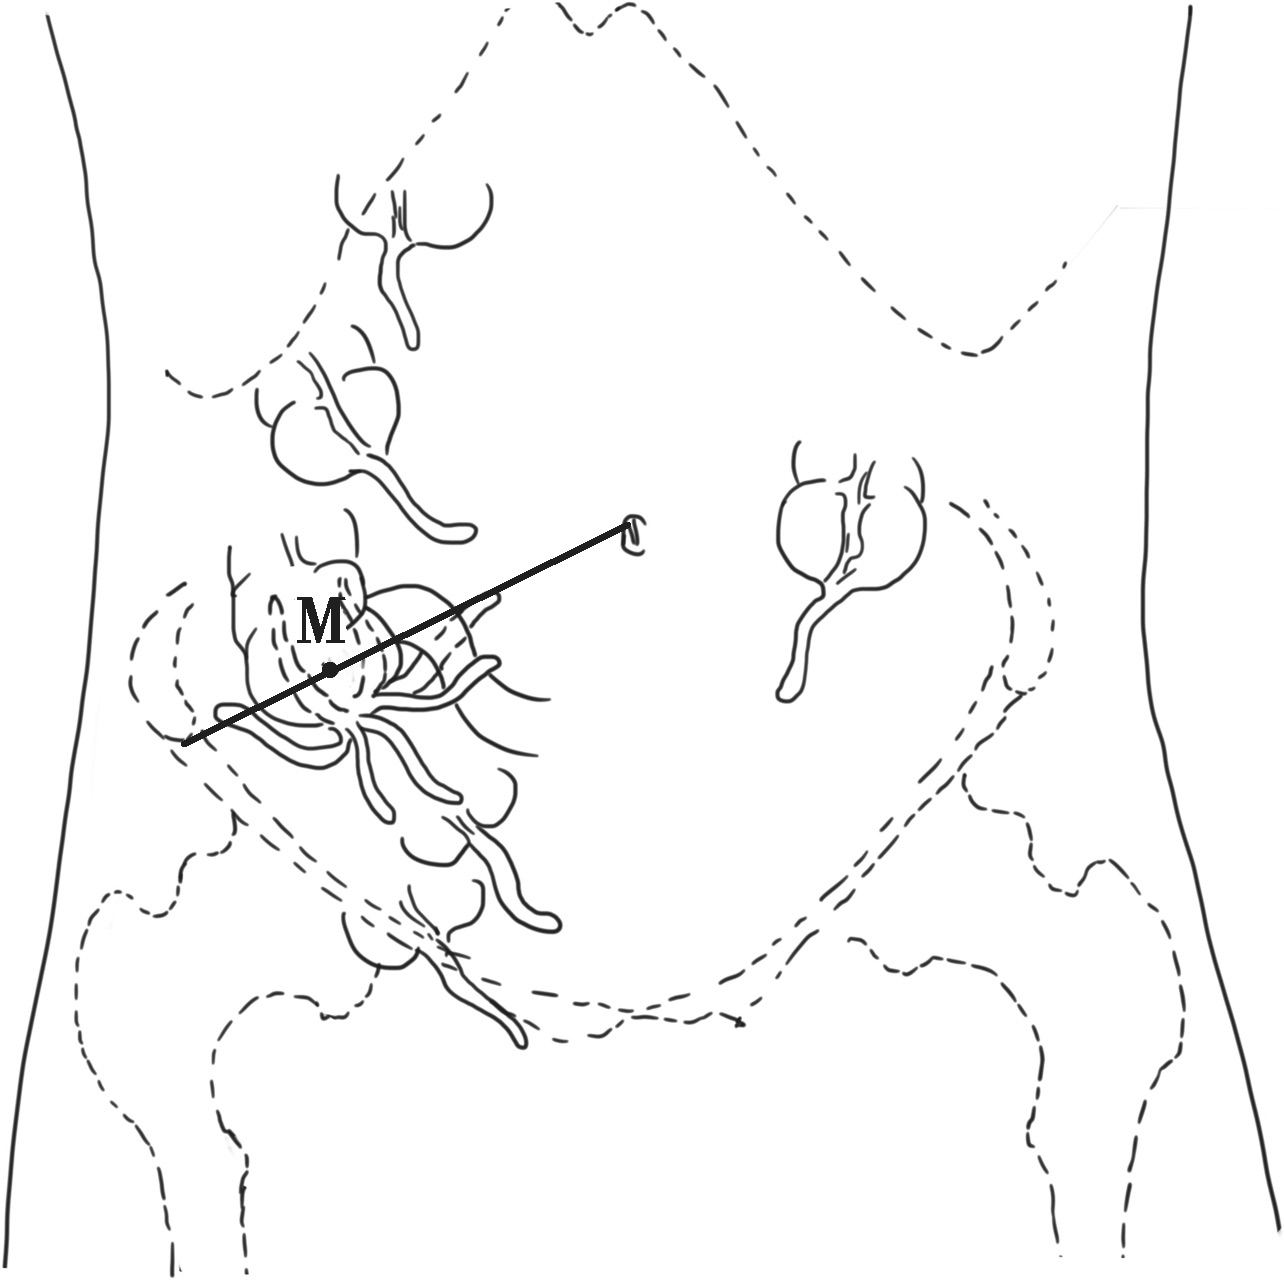

阑尾是附属于盲肠的一段肠管,多位于右髂窝内,长度一般为2~10cm,直径0.2~0.6cm,形态变异大。阑尾是腹膜内位器官,有三角形的系膜悬于肠系膜下端,阑尾根部连于盲肠后内侧壁,较固定,是3条结肠带汇聚的位置。因其尖端位置可变,炎症时产生的症状、体征也不同。据统计,国人阑尾常见位置有(图2-3):①回肠前位,约占28%;②盆位,约占26%;③盲肠后位,约占24%;④回肠后位,约占8%;⑤盲肠下位,约占6%;⑥高位阑尾(肝右叶下方)、盲肠壁浆膜下阑尾及左下腹阑尾,极少见。

图2-3 阑尾位置的变异(M为麦氏点)